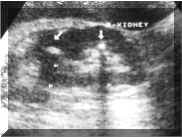

Sonographically,

stones

usually

appear

as

a

hyperechoic

foci

with

distal

acoustic

shadowing

(Picture1).

Picture1.

Two

in

kidney.